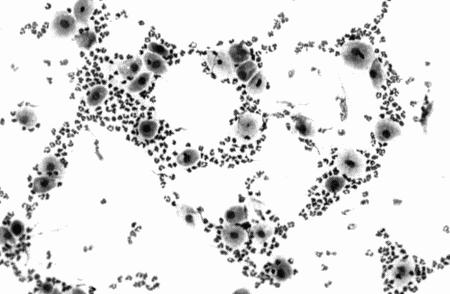

Вагинальная эндоскопия

Прекращение секреции эстрадиола фолликулами и переход их к секреции прогестерона приводят к снижению как отечности, так и васкуляризации слизистых оболочек, что сопровождается выраженным изменением характера вагинальных выделений, выявляемым с помощью вагинальной эндоскопии. На стадии проэструса слизистая оболочка становится более выпуклой и отечной, затем наблюдается ее уменьшение; по мере приближения овуляторного пика слизистая сжимается и бледнеет, в некоторых случаях становясь практически белой (фиг. 1.1). Перечисленные изменения свидетельствуют о приближении стадии, характеризующейся постепенным повышением концентрации прогестерона перед овуляцией и последующим наступлением фертильного периода. Эти изменения легко узнать, имея даже небольшую практику (фиг. 1.3), кроме того, они настолько воспроизводимы, что по набору признаков их можно оценивать полуколичественно. Вагинальная эндоскопия весьма полезна в определении оптимальных сроков вязки. По окончании фертильного периода, т. е. в начале метэструса — слизистая оболочка влагалища бледнеет и истончается, складки становятся закругленными — и что, вероятно, является наиболее характерным признаком, — слизистая в переднем отделе влагалища выглядит раздраженной и при прикосновении быстро сжимается, образуя розетку.

Фиг. 1.3.

Эндоскопическое исследование слизистой влагалища. Динамика изменений на протяжении цикла: (а) проэтрус — розовая окраска и отечность; (b) начало эструса — слизистая бледнеет, отек начинает уменьшаться (обычно перед пиком ЛГ); (c) середина эструса — слизистая бледная, уменьшение отека (сморщивание) явно выражено, что соответствует середине фертильного периода; (d) начало метэструса — видны закругленные складки, при прикосновении слизистая смыкается, образуя розетку (е) (см. Приложение)